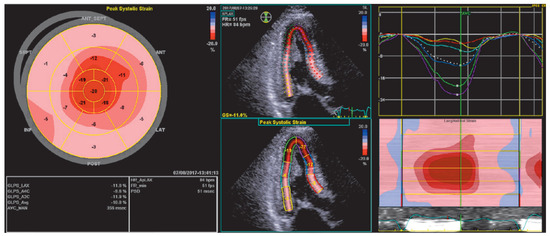

Echocardiography is key in detecting cardiac involvement in amyloidosis. Ohen, a hypertrophic cardiomyopathy is initially suspected on the basis of increased wall thickness and low ventricular volume (Figure 2). Tissue Doppler and strain measurements are especially important to detect diastolic and systolic dysfunction as patients initially present with HFpEF. The ventricle will first show diastolic dysfunction (Figure 3) due to noncom-pliance of the infiltrated myocardium, and in more advanced stages systolic dysfunction. Cardiac amyloidosis is characterised by regional variations in longitudinal strain, typically with apical sparing (Figure 4). Also a “granular sparkling appearance” of the leh ventricle is typical (important: switch off second harmonic imaging, as it may produce sparkling appearance in non-amyloidosis patients). Doppler measurements show restrictive filling patterns with increased leh ventricular filling pressures. Additionally the aortic and mitral valves appear thickened (amyloid deposits), as well as the intra-atrial septum and the right ventricle. The atria are typically dilated and quite ohen a pericardial effusion is found. The combination of echocardiographic signs of hypertrophic cardiomyopathy and a normal or low voltage ECG have a high sensitivity and specificity for amyloidosis [9,10,11].

Figure 4. Speckle tracking echocardiographic example of impaired peak systolic strain and the typical ‘bulls eye’ showing ‘apical sparing’.